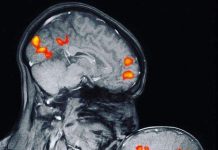

Exame mostra a ligação entre mãe e filho pela primeira vez no mundo

Em um exame de ressonância magnética que foi realizado no laboratório do Instituto de Tecnologia de Massachusetts, nos Estados Unidos, detecta a reação hormonal no cérebro...